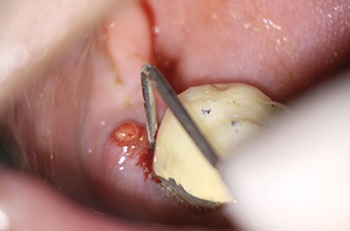

Case 3: A lateral lesion with a superficial crack

This patient presented for a second opinion after an endodontist recommended extraction for tooth #31 because of a VRF on its distal root. A deep isolated probing defect, a cervical sinus tract, the lateral position of the periradicular lesion and the prior placement of a full crown because of cracks in the tooth’s distal enamel marginal ridge likely contributed to the prior diagnosis of VRF.

A new diagnosis of previously treated and chronic apical abscess was made, but the possibility of a VRF was discussed with the patient. RCT was initiated. Internal examination of the pulp chamber reassuringly revealed that a crack on the distal wall of the pulp chamber did not extend to the pulpal floor. Treatment was completed in three visits using a calcium hydroxide intracanal medicament. Treatment and postoperative radiographs revealed a sharp dilaceration of the distal root, likely focusing the bony lesion toward the distal surface, not toward the root apex. Four months later, soft tissue and bony healing were confirmed.

Endodontic Root Fracture Case Series

Fig. 9: Preop PA.

Fig. 10: Preop CBCT.

Fig. 11: Preop probe.

Fig. 12: Recall PA.

Fig. 13: Recall CBCT.

Fig. 14: Recall probe.